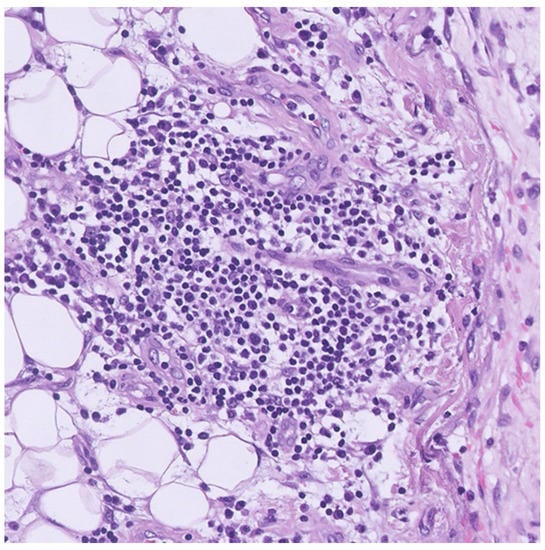

2. Case Presentation